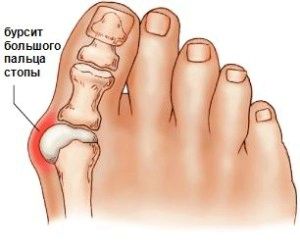

Але з віком відбуваються певні зміни, що впливають на вигляд ноги, викликаючи цим дискомфорт. У деяких жінок з віком близько великого пальця утворюється шишка - так починається бурсит стопи.

Така освіта називається бурсит великого пальця. Поразка суглоба в даній області відбувається поступово. При запущеній стадії хвороби ця шишка костеніє, виникають болі через запального процесу, що відбувається всередині. В результаті людині складно підібрати взуття, в якій було б зручно ходити.

Бурсит великого пальця стопи викликає деформацію суглоба. Відбувається нахил пальця, і утворюється пухлина. На нозі це виглядає як випинання кісточки біля великого пальця. Іноді суглоб деформується настільки, що відбувається зсув. При цьому сусідній палець випинається наверх.

Запалення великого пальця стопи починається з невеликого м'якого освіти в цій галузі. Змінюється естетичний вигляд ноги. Згодом шкіра червоніє і виникають болі. Відсутність своєчасного лікування дозволяє хворобі прогресувати далі.

Відбувається деформація великого пальця, і він викривляється. Згодом утворюється тверда шишка, або кісточка, як її називають в народі. Утворюється так звана кісткова мозоль. Шкірні покриви знаходяться в стані хронічного роздратування. Виникають постійні болі, що заважають пересуванню. Деформуються інші пальці.